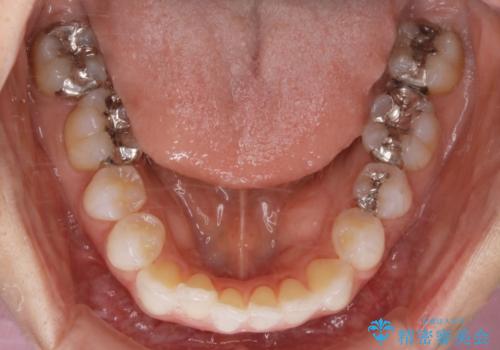

- 前歯のガタつき改善を主訴にご来院されました。

ガタつき自体は軽度で、奥歯の噛み合わせのズレもほとんどなかったため、非抜歯でマウスピース矯正装置を選択しました。

歯列の幅の拡大と歯を小さくする調整を行うことで並べるスペースの確保を行いました。この方法は、ガタつきをとりたいところに直接スペースを作ることができるので治療期間を短縮することができ効率的です。

歯列弓の拡大

歯並びが悪くなる原因の一つに「歯列弓の狭窄」というものがあります。

奥歯や前歯が内側(舌側)に倒れ込んでしまったり、歯が生えてくる位置が内側になってしまうことにより歯並びのアーチが狭くなってしまうことを言います。

このような場合、歯並びのアーチを拡大してあげるだけでもガタつきを無くすためのスペースがかなり作れることがあります。